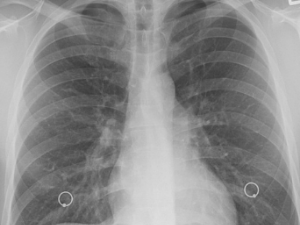

폐에 물이 차는 것을 폐부종이라고 합니다. 폐부종은 폐포라고 알려진 폐의 기낭에 체액이 비정상적으로 축적될 때 발생합니다. 이로 인해 호흡 곤란과 산소 교환 장애가 발생할 수 있습니다.

폐부종의 증상으로는 호흡 곤란, 기침, 천명음, 질식 등이 있습니다. 이는 즉각적인 치료가 필요한 심각한 상태입니다. 치료는 근본 원인에 따라 달라지며 과도한 체액을 제거하거나 심장 기능을 개선하거나 문제의 근본 원인을 해결하기 위한 약물 치료가 포함될 수 있는데요. 여기에서는 폐에 물이 차는 증상 원인 8가지/폐에 물이 찼을 때 치료 방법 10가지를 알아보겠습니다.